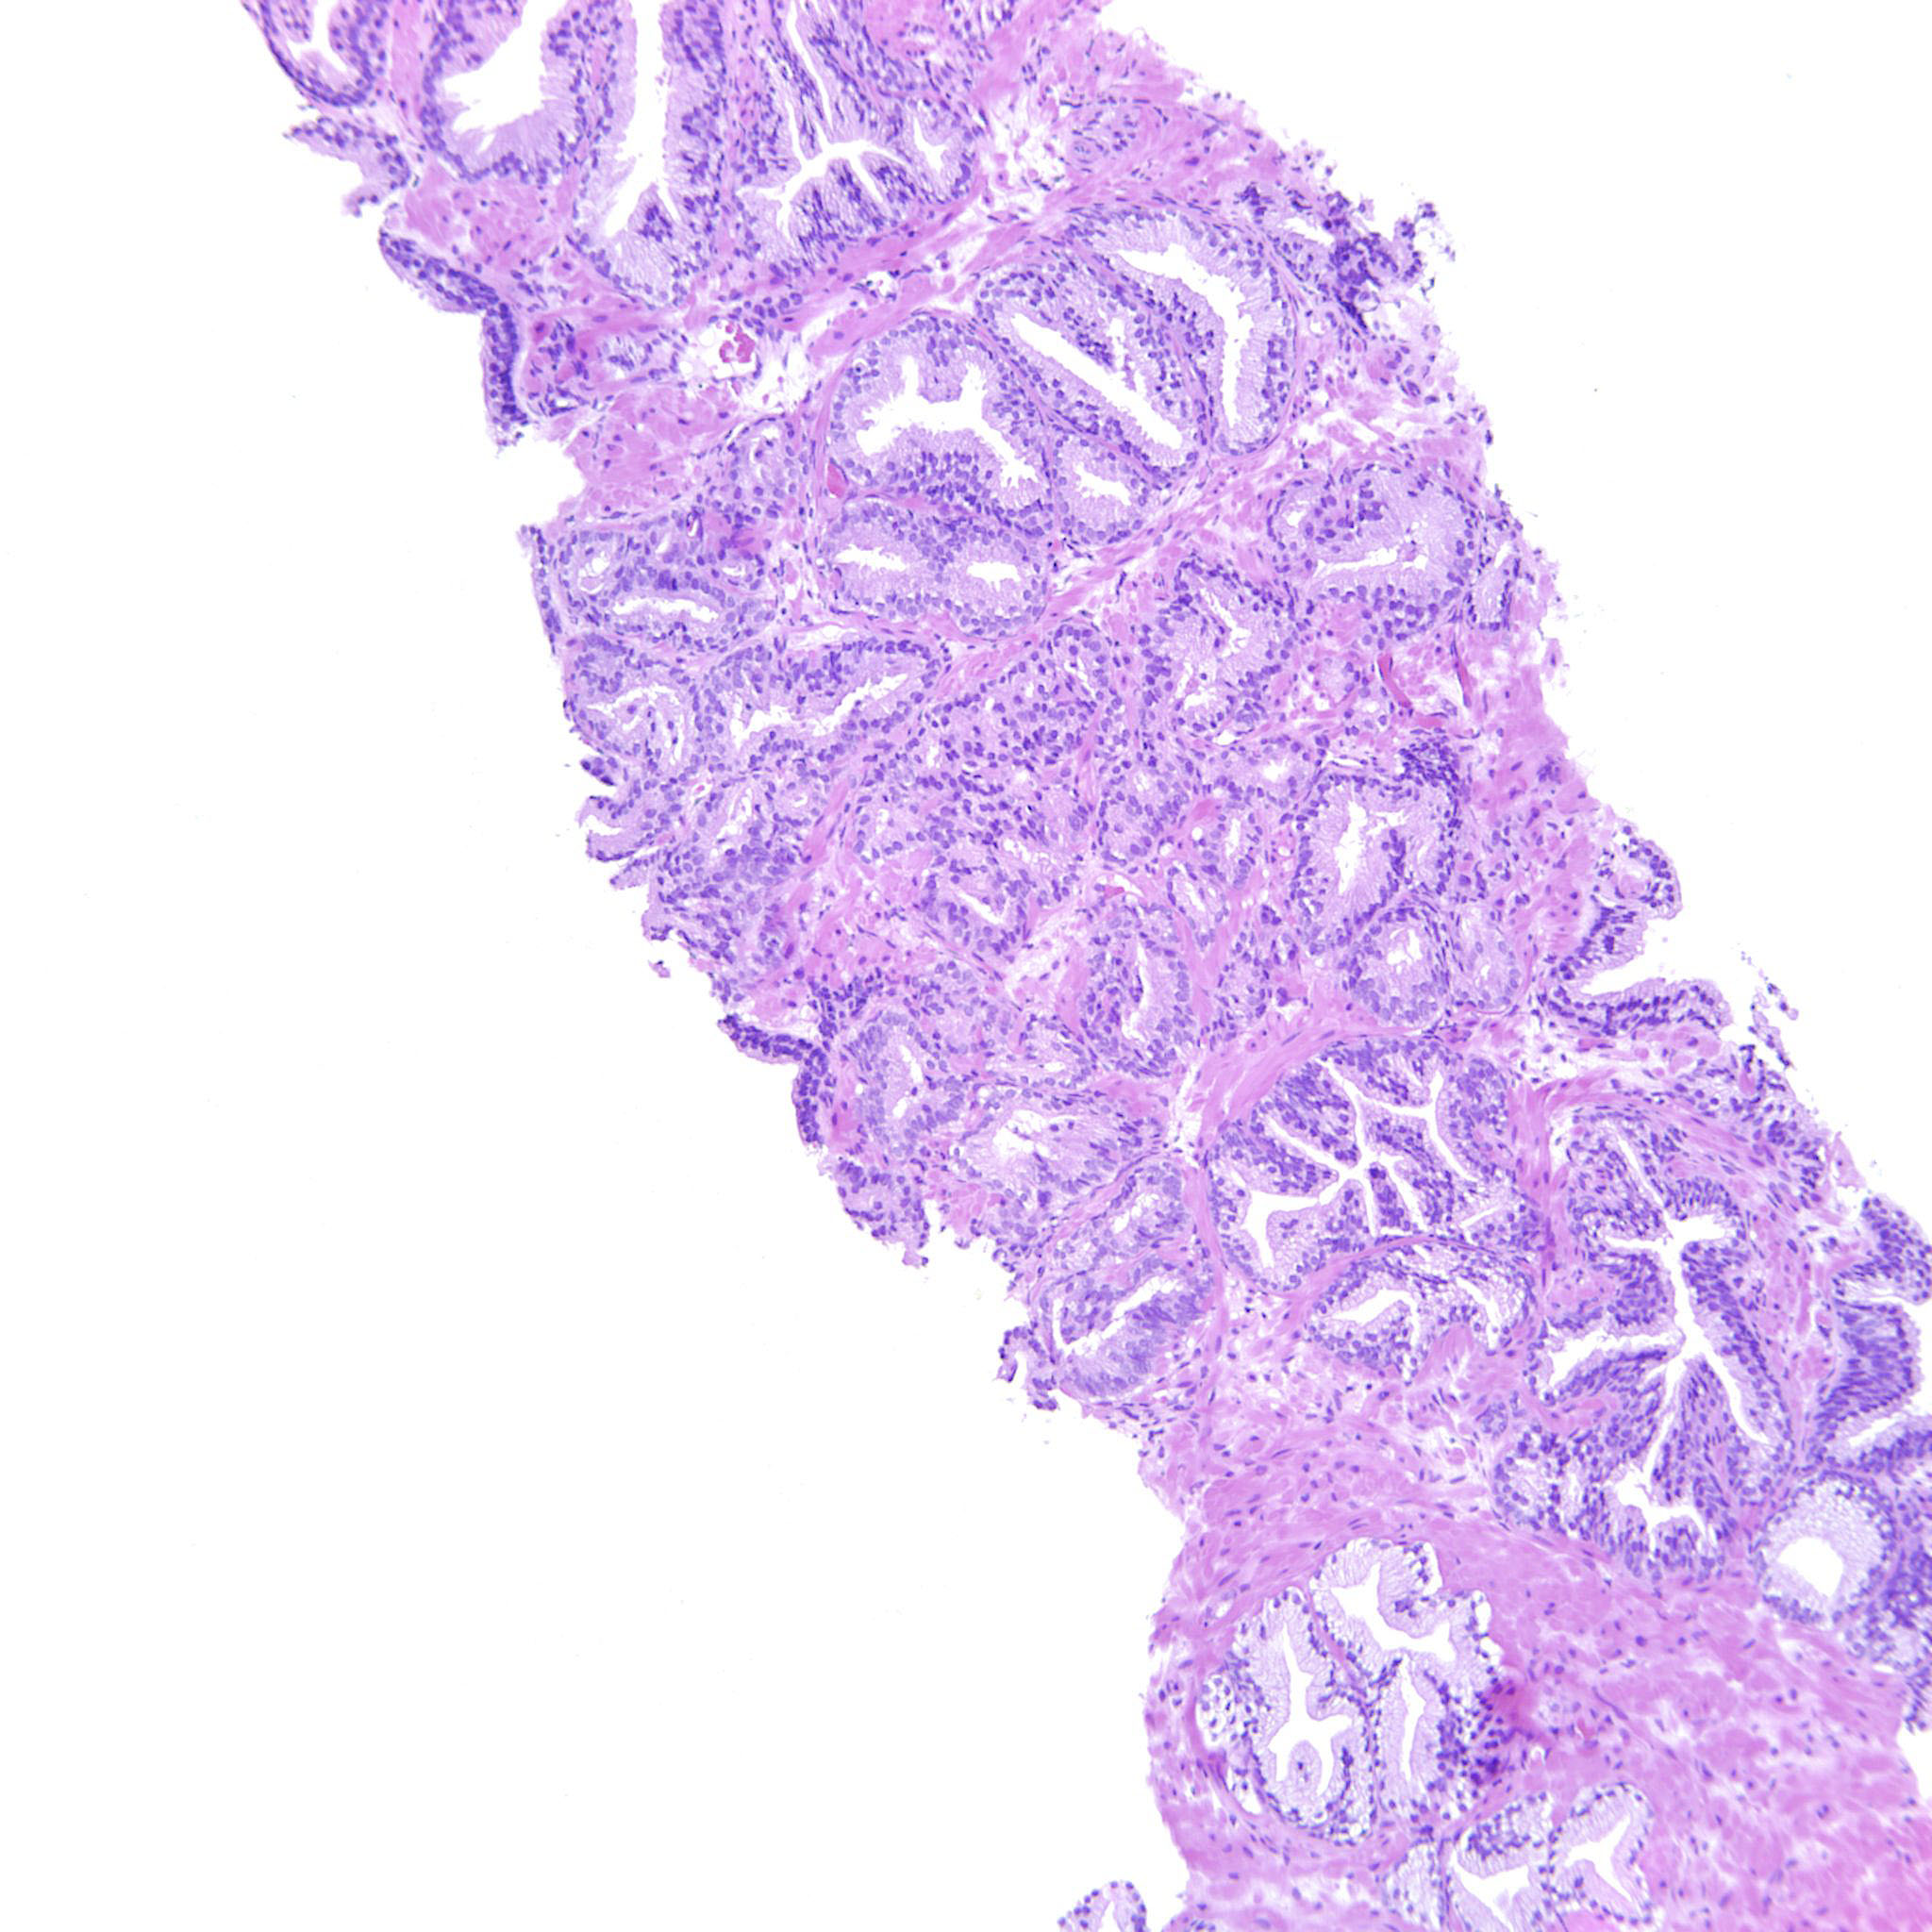

Prostate cancer grading

Case ID: 738